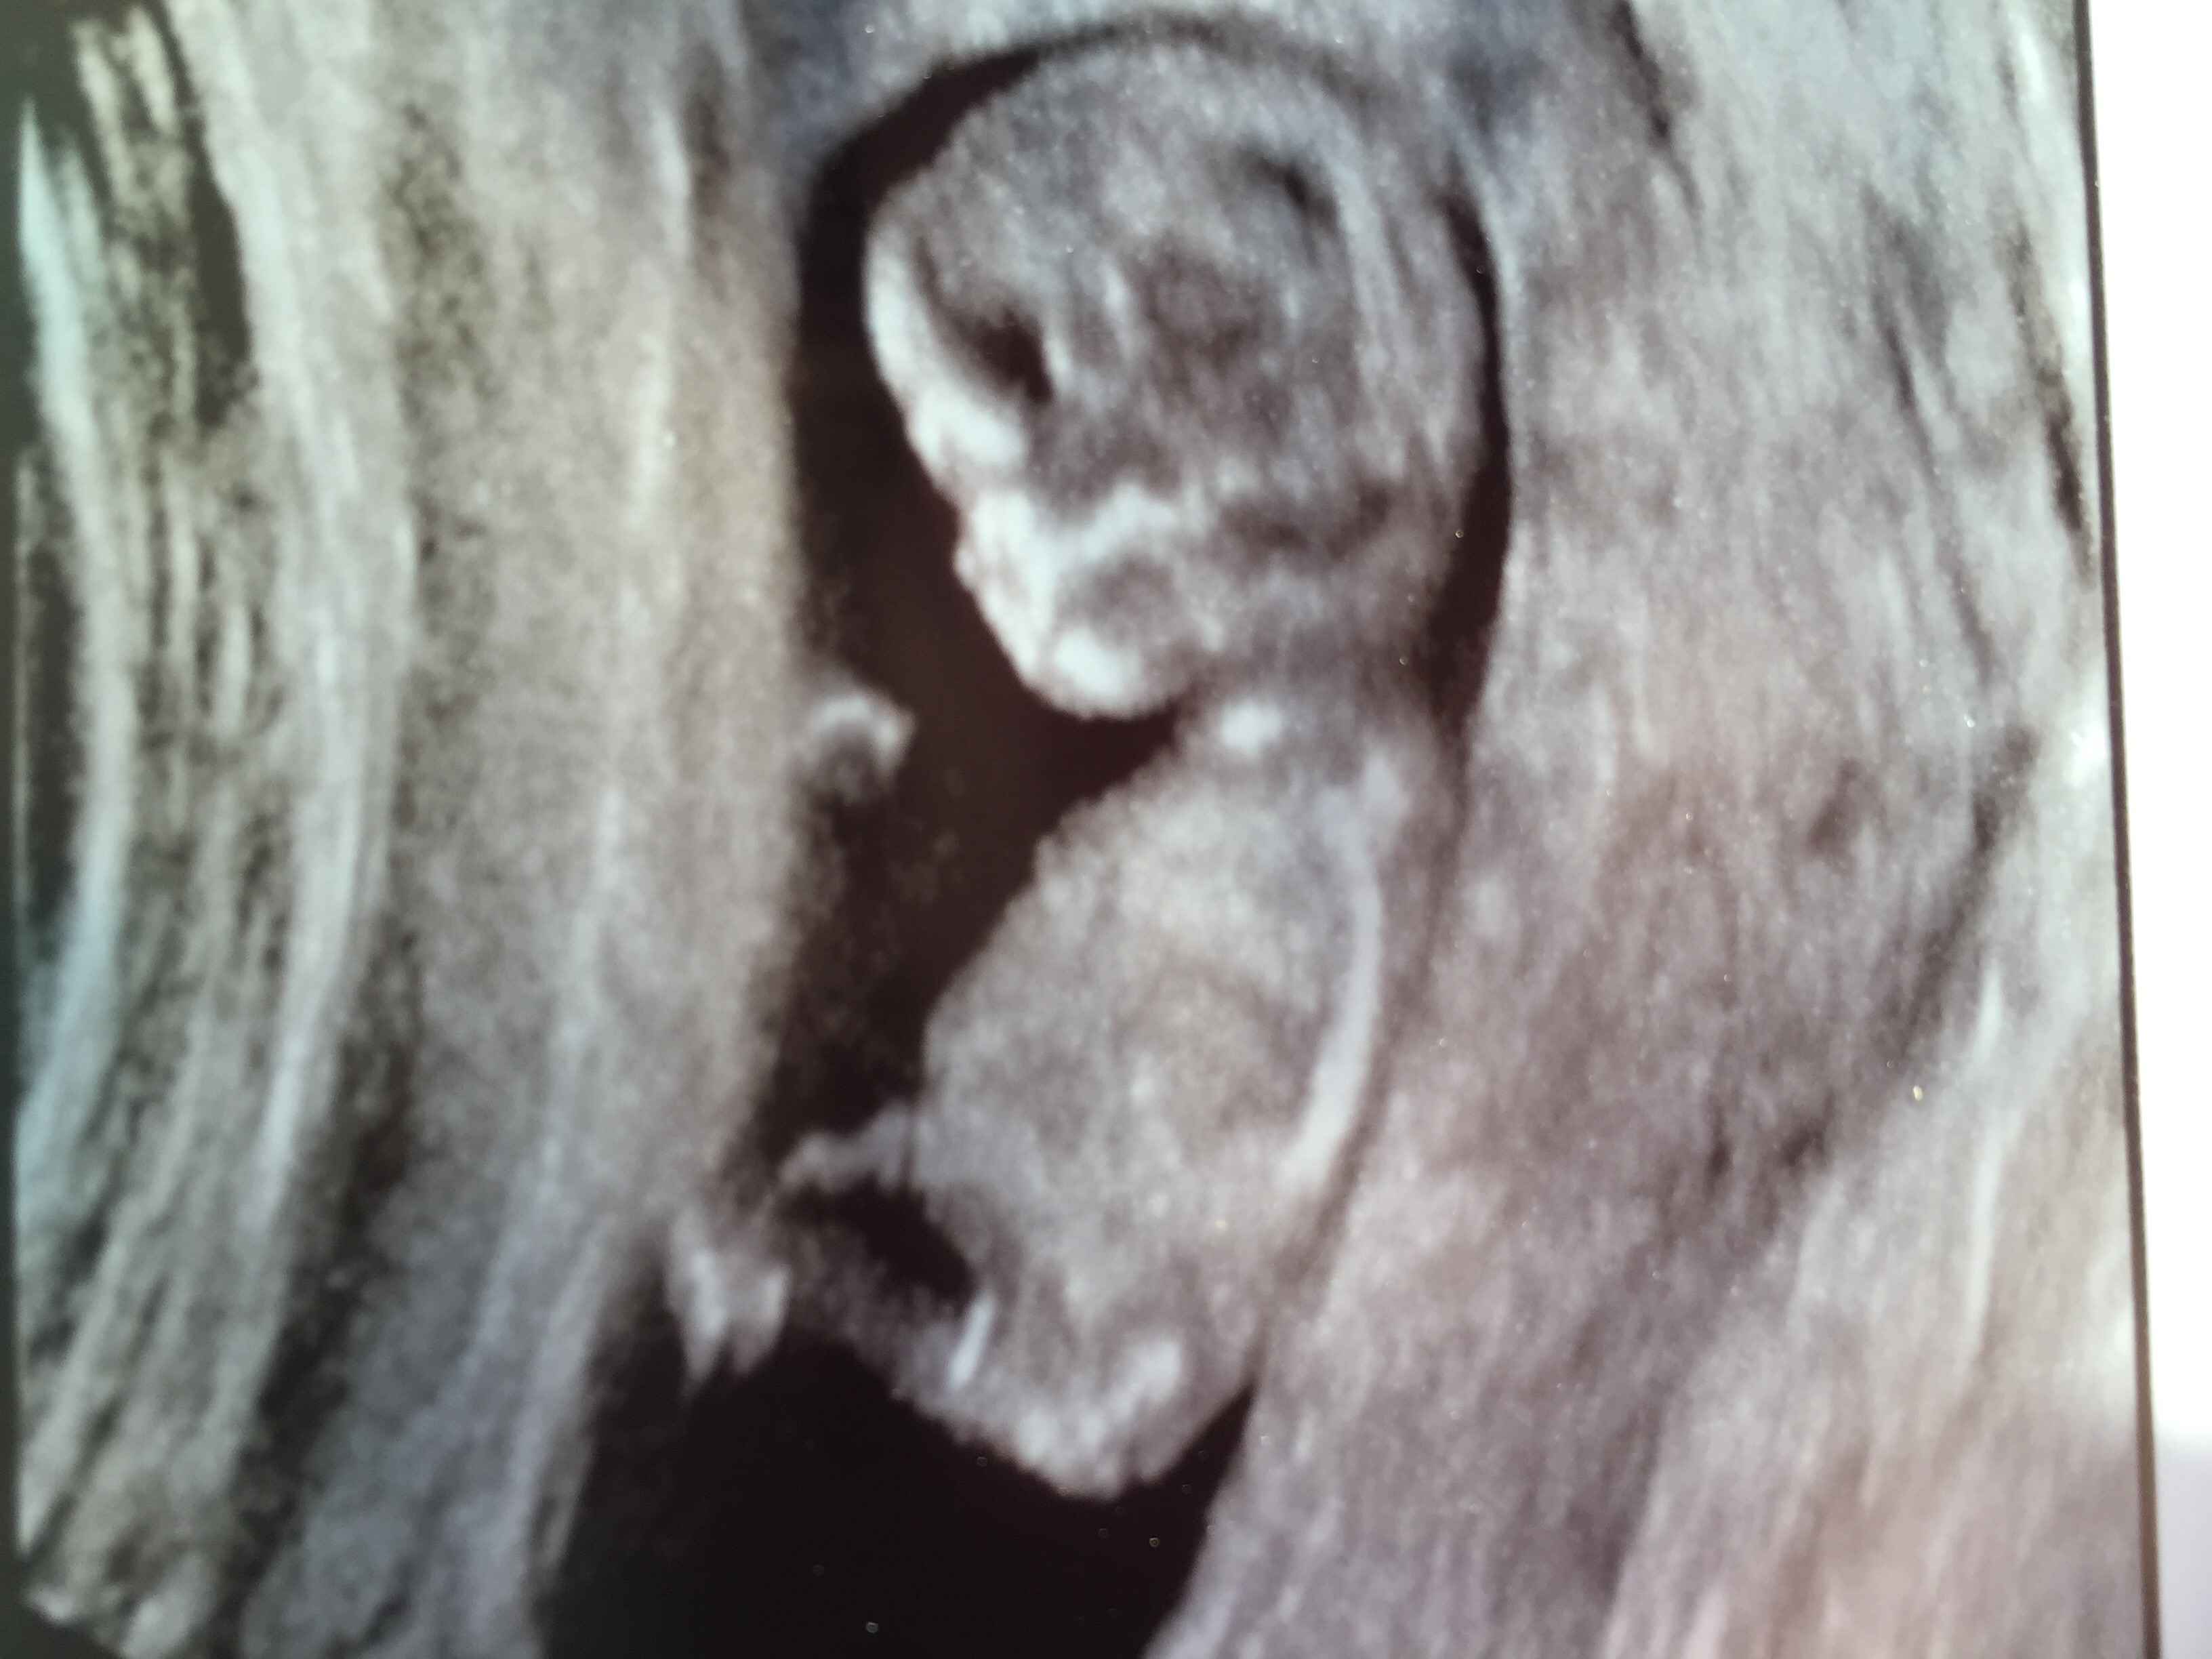

12 weeks 2 days, what do you think?!